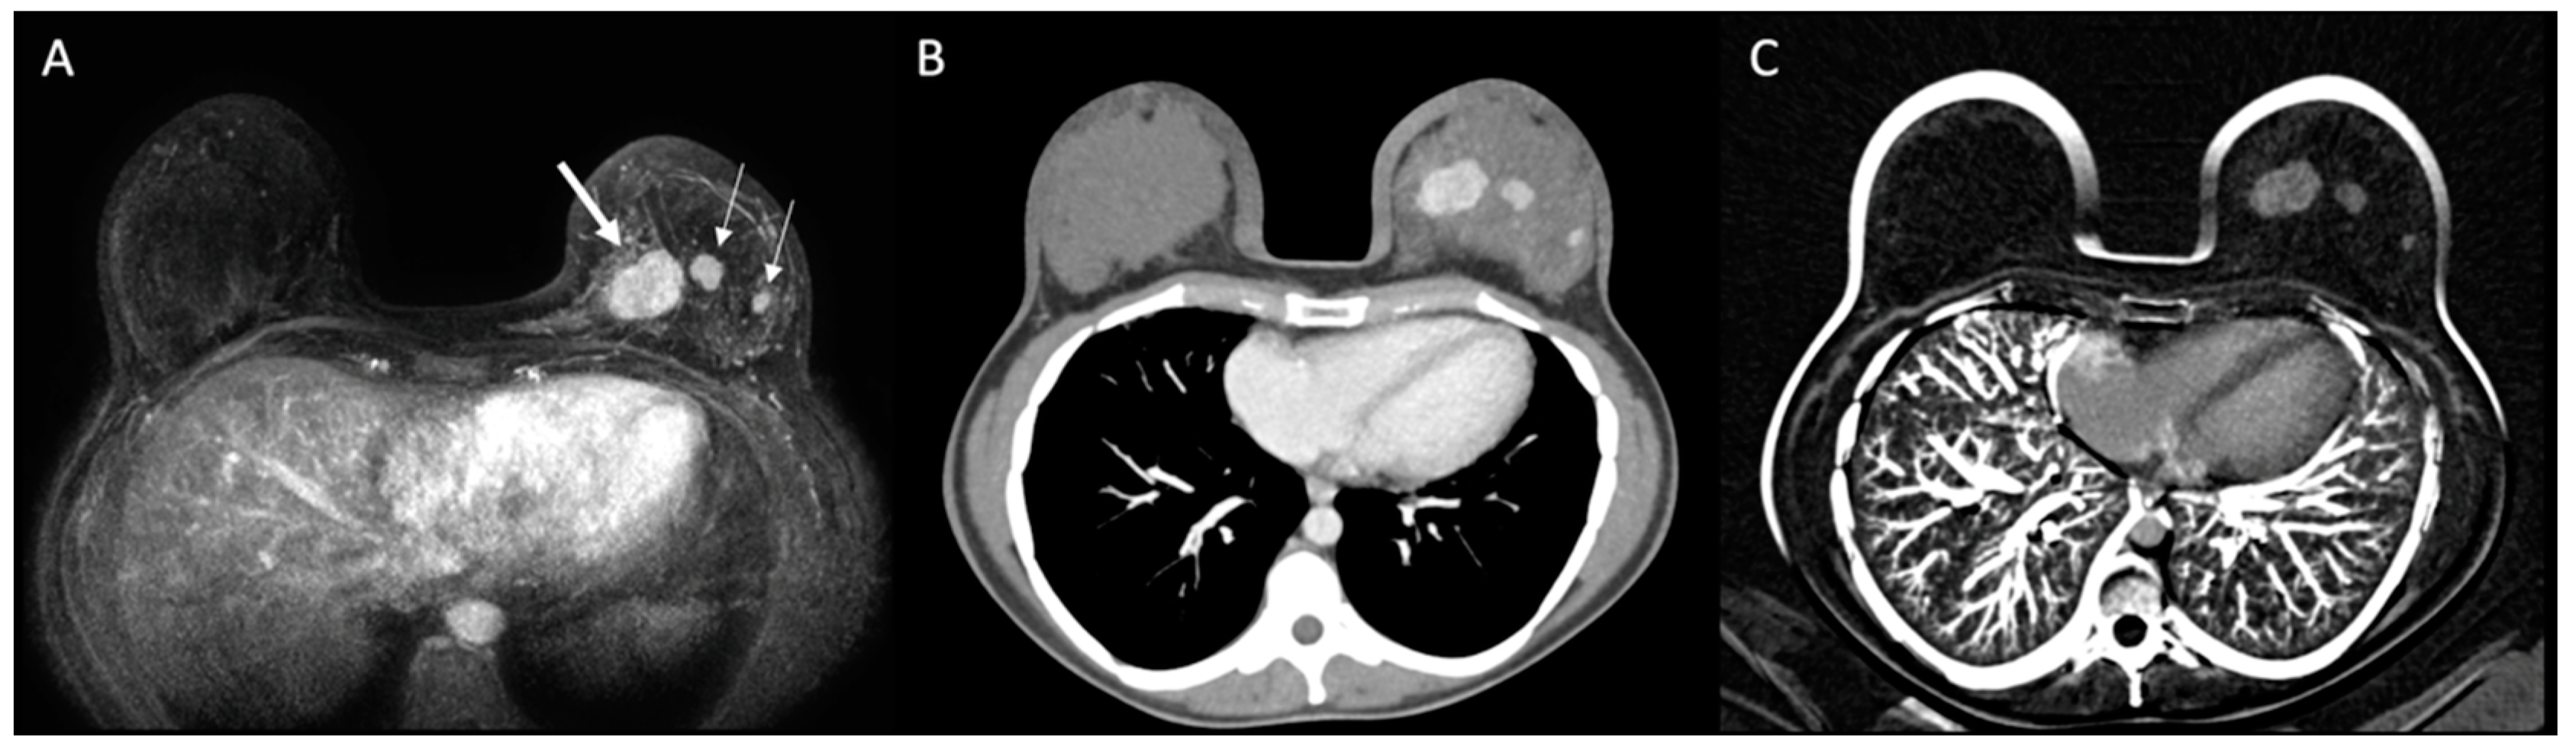

2.3. Imaging Acquisition

2.4. Image Analysis